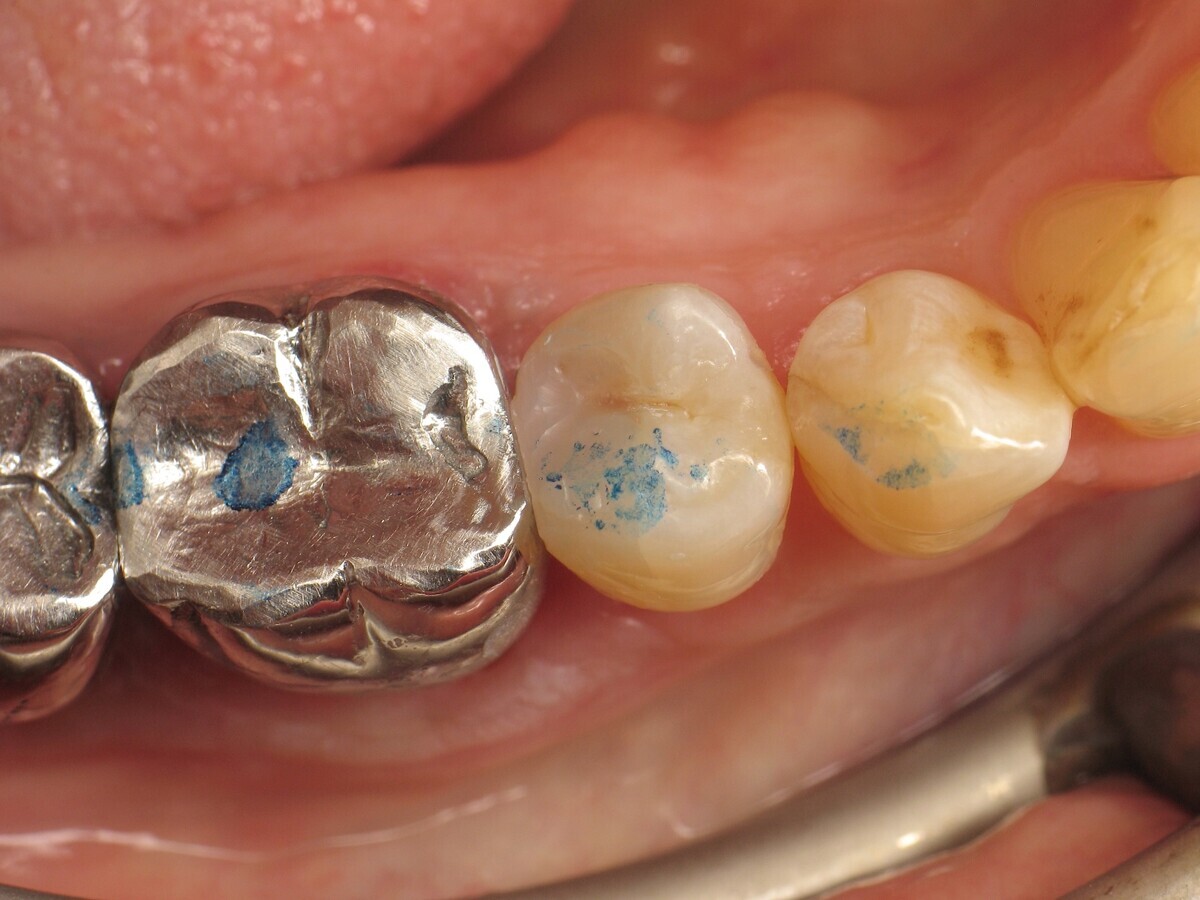

Antes y después. Izquierda: situación inicial del premolar con caries de clase II. Derecha: restauración finalizada y pulida. Fotografías: Yassine Harichane

El caso clínico descrito en este artículo se refiere a una cavidad de clase II en un premolar (45) que será restaurada con un composite termoviscoso (Figura 1).

Figura 01. Premolar con caries de clase II.

Para ajustar la oclusión, se utiliza papel articular para visualizar los puntos de contacto (Figura 20) y realizar las correcciones necesarias (Figura 21). El resultado final es muy natural (Figura 22).

Figura 20. Control de oclusión antes de los ajustes.

Figura 21. Control de oclusión después de los ajustes.

Figura 22. Restauración completada después del pulido.